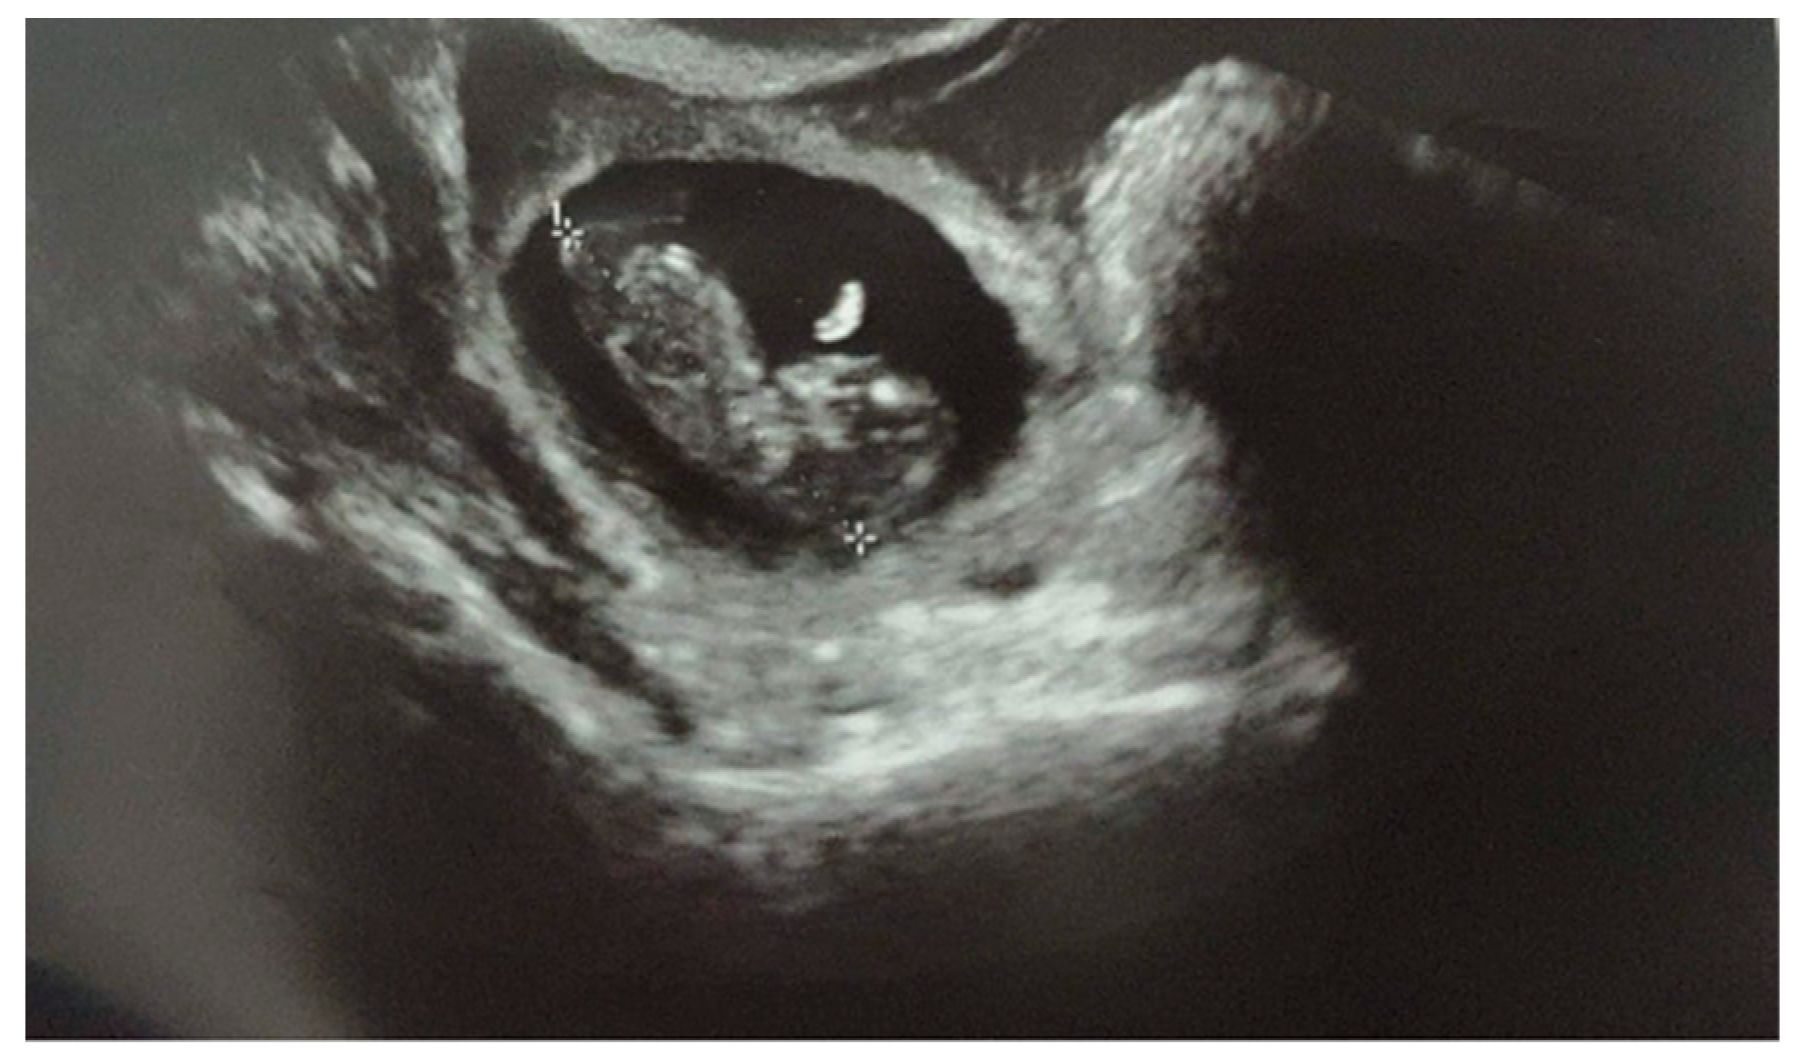

When she came to our institution, her vital signs were stable. She showed no sign or symptoms of rupture of the ectopic pregnancy. Blood samples were in range, and there were no signs of shock. The physical examination revealed a soft abdomen with no tenderness or rigidity. The ultrasound examination demonstrated a gestational sac in the right tubal area, containing an embryo of 10 + 4 weeks’ (Crown Rump Length of 36.7 mm) (Figure 1). Fetal heartbeat was present. No intrauterine pregnancy was noted. There was a 35 mm layer of free fluid in the pouch of Douglas. Since the diagnosis was already evident, the beta-HCG levels were not measured.

Figure 1. Ultrasound examination demonstrating a 10 + 4 weeks’ tubal pregnancy with a fetal heartbeat.